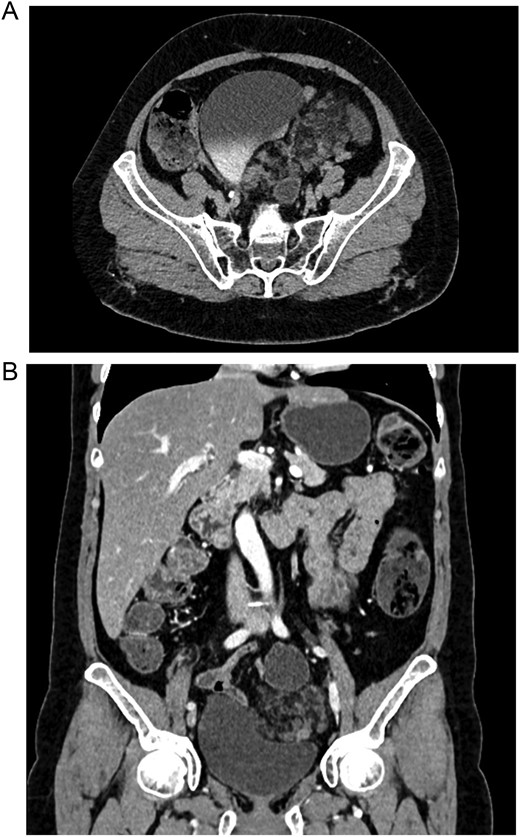

On physical examination, a stable patient with abdominal pain was encountered. The patient’s abdomen revealed tenderness in her lower abdomen, and on genital palpation, a hard retro-cupular 3 × 3 cm mass was palpable and slightly painful upon mobilization. Due to this, a transvaginal ultrasound was requested, revealing a 10 × 4 cm mass appearing to arise from the vaginal cuff. A contrast-enhanced computed tomography (CT) was done to delineate this image further, showing a 10 × 5 × 4.7 cm mesenteric mass with heterogeneous densities attached to the vaginal cuff. It was also close to the bladder and bowel loops but without invading it, with changes in the density of fatty and soft tissues (Figs 1A and B and 2A and B).

(A) CT, the lymphangioma is seen with heterogeneous densities. (B) CT, coronal view of the lymphangioma close to the bladder.